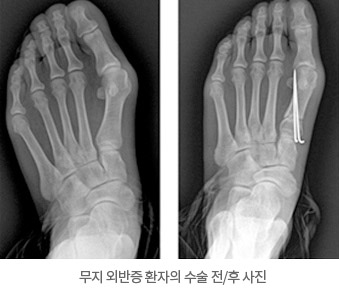

동통이나 변형이 심한 중등도 이상의 변형의 경우, 또는 보존적 치료에도 신발을 신기 어려울 정도의 일상생활에 지장이 있는 경우라면 수술적 치료의 대상이 됩니다. 수술을 통해서 훨씬 보기 좋고 안 아픈 발로 만들 수 있고 수술의 후유증이나 재발은 매우 적기 때문에 많이 사용되고 있습니다.

경증의 무지 외반증의 경우에는 중족골의 원위부에서 절골하는 원위부 갈매기 절골술을 단독으로 시행하거나 근위 지골 절골술을 병행하여 시행할 수 있습니다. 경증이거나 중등도의 무지 외반증의 경우 원위, 중위, 근위중족골 절골술중 하나와 원위부에서 연부 조직의 재정렬을 위한 수술을 같이 시행할 수 있고, 중증의 무지 외반증의 경우는 원위 연부 조직 수술과 더불어 중위나 근위에서 중족골의 절골술을 시행합니다.

무지 외반증 환자의 수술 전/후 사진